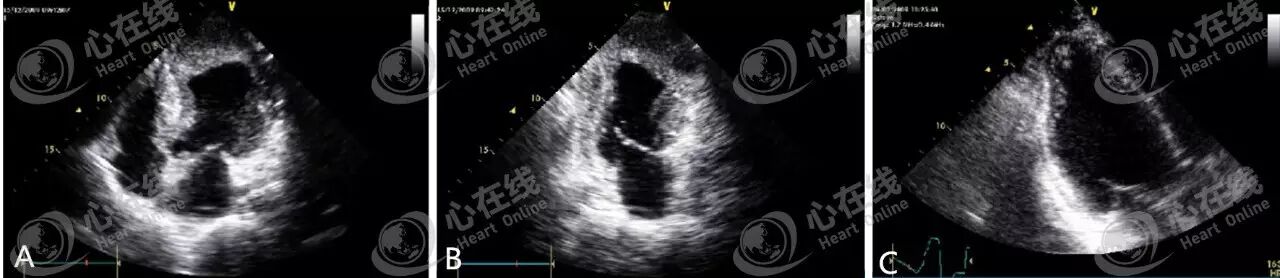

观察四心腔切面(图A)、两心腔切面(图B)、三心腔切面(图C),可见左室心梗后形成的各类型血栓,且均附着在左室心尖部。

观察图A可见心房内巨大的、多发的占位性病变,即左房血栓。图B显示游离的左房血栓,由于二尖瓣口狭窄,血栓不能通过,只能在左房里面反复运动。游离血栓非常危险,一旦血栓卡到二尖瓣口,就会完全堵住二尖瓣口血流,进而诱发阿斯综合症。此外,血栓在心腔内不断运动,血栓碎片不断脱落, 容易导致体循环栓塞。

观察图A可知心房内出现异常回声,且粘液附着部位多在卵圆孔附近。图B显示活动度较大的粘液瘤,部分粘液已经移动到左室,内部回声不均。观察图C可见大部分心脏结构于舒张期被拖至左室,易发生体循环栓塞。图D显示粘液附着部位在肺静脉入口,而不在卵圆孔附近。

观察图A可见室壁、室间隔厚度均明显增加,提示肥厚型心肌病。观察图B可见绿色箭头处室壁运动明显减弱,由冠心病、心肌梗死所致,我们称之为节段性的室壁运动异常。